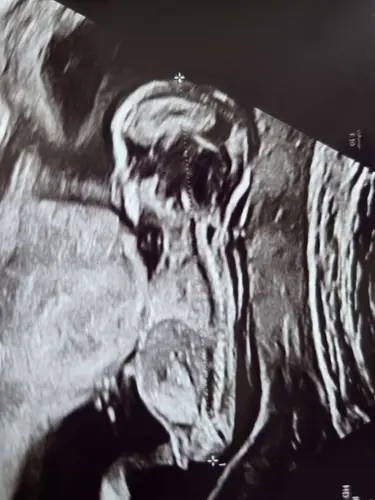

Nub theorie 13.3

Wat denken jullie? Kunnen jullie zien of het een jongetje is of een meisje? Zo spannend! Liefs

Jalad

Meisje